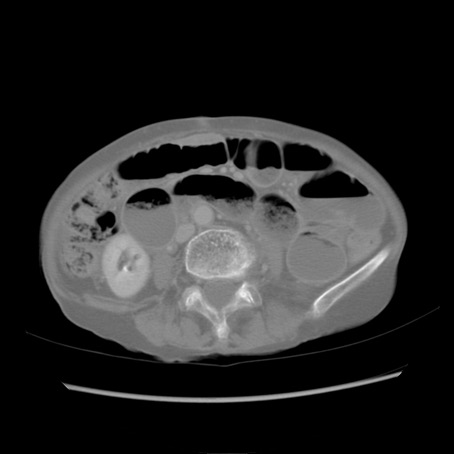

症例25(横断像)

症例

【症例】80歳代女性

【主訴】胸のつかえ感

【現病歴】約9時間前に食後から胸のつかえた感じあり、嘔吐あり、来院。

【既往歴】胃癌(全摘)、胆摘、虫垂炎

【身体所見】心窩部に圧痛あり、反跳痛なし。

【データ】WBC 5700、CRP 0.05